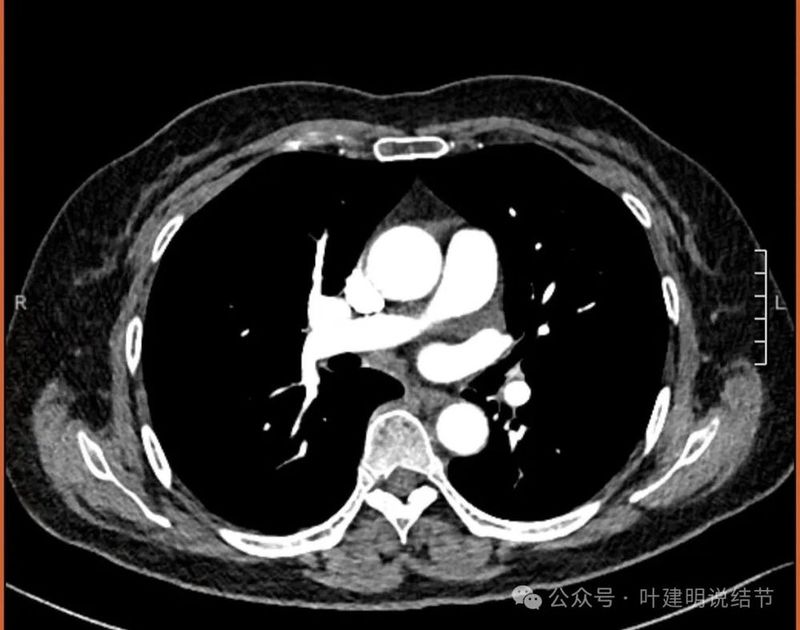

纵隔窗见有明显实性成分,磨玻璃成分不可见,走行血管也明显。

纵隔与肺门没有见到显著增大融合要考虑转移的淋巴结。